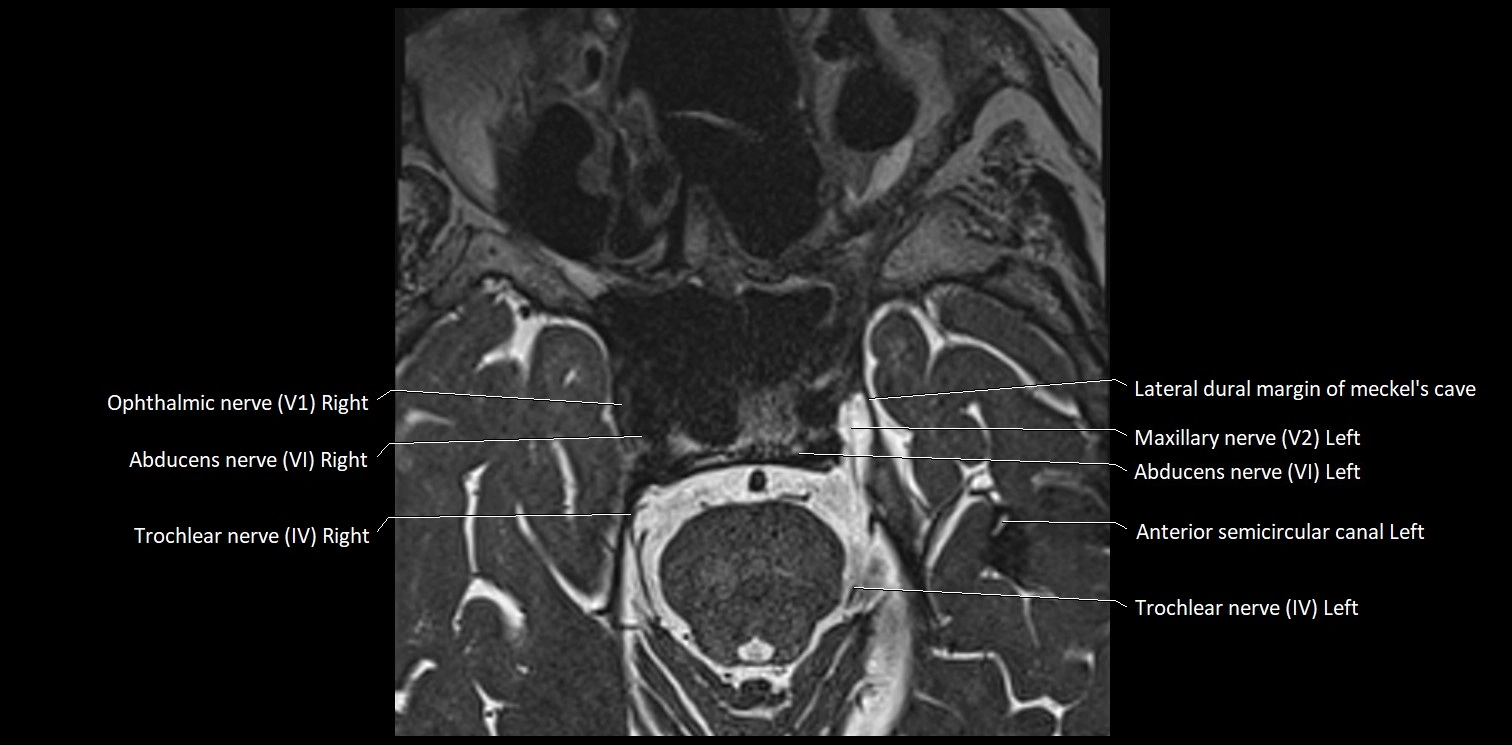

MRI images

image